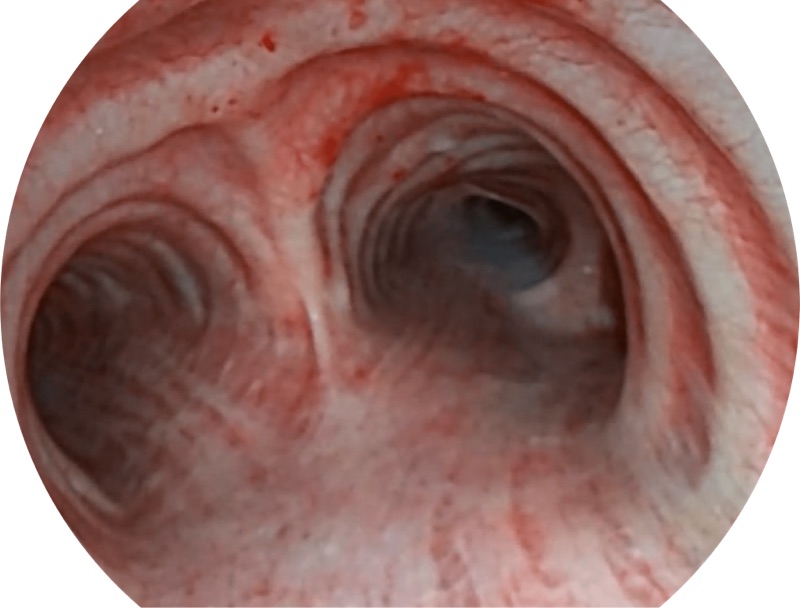

• 高清画质

帮助医生更加清晰地观察气管表面病灶